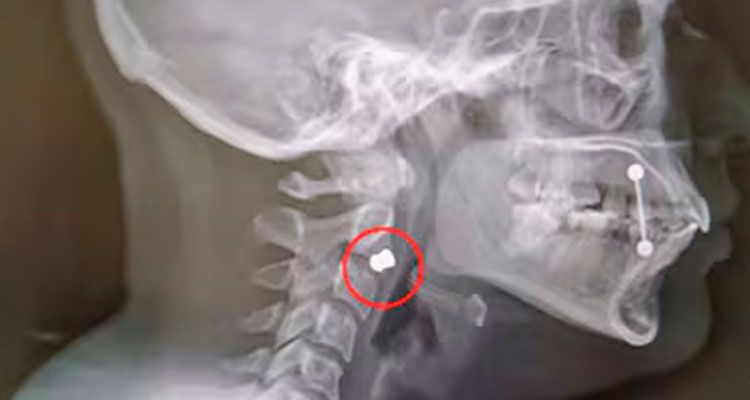

La noche del viernes 17 de abril, pasada la 1 de la madrugada, los imputados dispararon desde el cuarto piso del edificio ubicado en boulevard Chacabuco al 1000. Alessio, estudiante de arquitectura, reside en ese departamento. Hasta allí llegó Montes, estudiante de abogacía. Las víctimas fueron Orlando Vélez, un repartidor de 29 años que recibió un impacto en la espalda, y Milagros Farías, de 23 años, quien terminó con un balín de plomo alojado en la zona anterior de la mandíbula, en el borde alto del cuello.

Desde el Poder Judicial señalaron a PERFIL CÓRDOBA que la aparición de una segunda víctima con un proyectil alojado junto a la segunda vértebra cervical cambió radicalmente el análisis jurídico del caso. La fuente precisó que la figura del placer -primer supuesto del inciso 4 del artículo 80- resulta aplicable cuando el autor actúa para divertirse, y que en este caso no existió error ni confusión: los imputados utilizaron a personas como blanco de manera deliberada. "No fue por error, estaban con la escopeta disparándole a la gente", describió la fuente judicial.

Respecto a la situación de Farías en particular, la fuente anticipó que se aguardan los informes médicos para definir si la calificación puede elevarse de lesiones leves a graves. Los factores que analiza la fiscalía incluyen la necesidad de una cirugía -probablemente con anestesia general-, la localización del proyectil en el rostro y la posibilidad de una deformación permanente, que constituye uno de los parámetros legales para encuadrar el hecho en el tipo penal más severo.